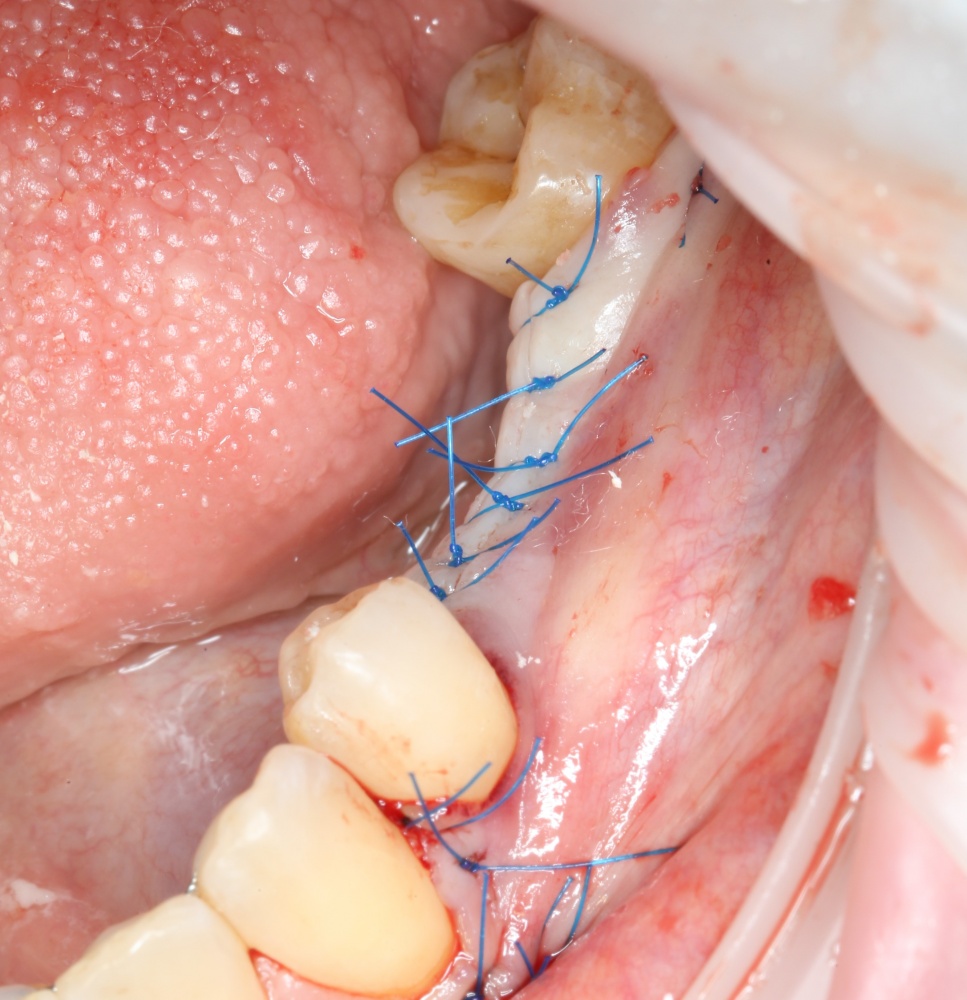

Ну и, швы. Если все сделать правильно, рана сложится сама, без лишних усилий:

A09A5472 (2) A09A5475 (2)

В послеоперационном периоде ведение раны и назначения такие же, как при обычной операции остеопластики.